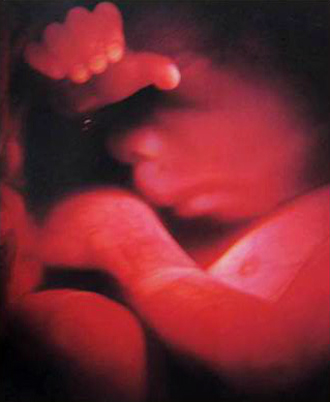

- 산전진찰 및 복부 초음파 (1회/2주)

- 막달 산모 종합 검사 (35~36주)

- 태동검사 (34~36주)